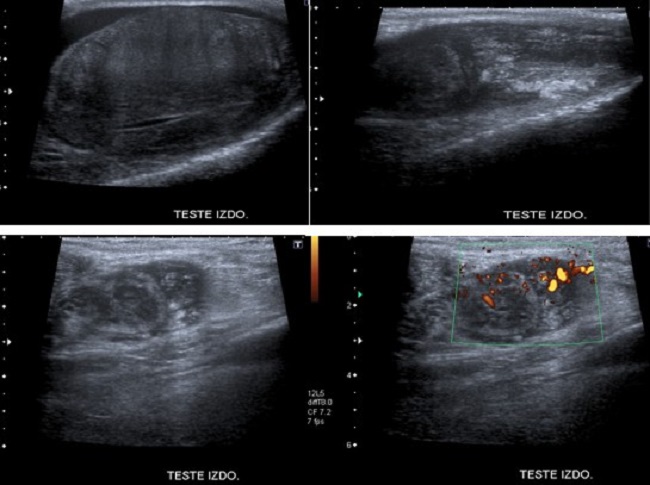

Paciente de 55 años, antecedentes de ser fumador cinco cigarrillos/día, bebedor ocasional, hipertensión arterial en tratamiento con olmesartan 20mg/día. Acude a consulta por presentar aumento del volumen del hemiescroto izquierdo de un año de evolución. A la exploración física en la inspección impresiona un hidrocele, pero a la palpación presenta teste izquierdo aumentado de tamaño, indurado, tacto rectal se palpa una próstata aumentada de tamaño, superficie regular, bien delimitada, fibroadenomatosa G-II. En la analítica el hemograma, leucograma, marcadores testiculares: β-HCG, CEA, AFP, función renal, hepática y pancreática normales, aumento de la lactato deshidrogenasa (LDH). Se le realiza ecografía escrotal y testicular que informa: Teste derecho de unos 47x15 mm, sin identificar alteraciones patológicas significativas del epidídimo. Teste izquierdo de unos 55x28 mm, con ecogenicidad muy heterogénea, presentando zonas de mayor ecogenicidad, y otras de menor, de forma difusa, sin identificar claramente lesiones nodulares. Marcado engrosamiento difuso de todo el epidídimo, con alteración de la ecogenicidad, y vascularización incrementada. Abundante líquido en cavidad escrotal (Figura 1).